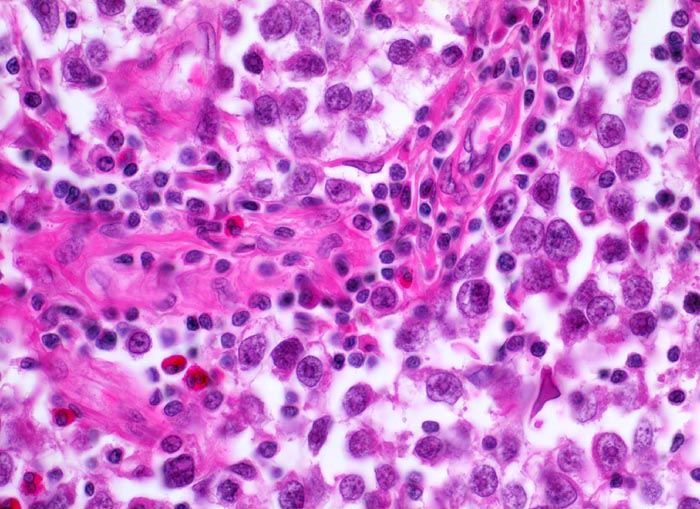

Seminom des Hodens

Aufgrund der suboptimalen Fixation sind die Tumorzellen diskohäsiv und das Zytoplasma ist geschrumpft. Die Tumorzellen haben grosse hyperchromatische Kerne mit einem typischen grossen zentralständigen eosinophilen solitären Nukleoli. Ebenfalls typisch das begleitende überwiegend lymphozytäre Entzündungsinfiltrat und einzelne eosinophile Granulozyten.

Makroskopisch aus mehreren Knoten bestehender weisser Tumor von 2cm Durchmesser.

Der Patient suchte den Arzt wegen einer schmerzlosen Hodenvergrösserung auf.

400